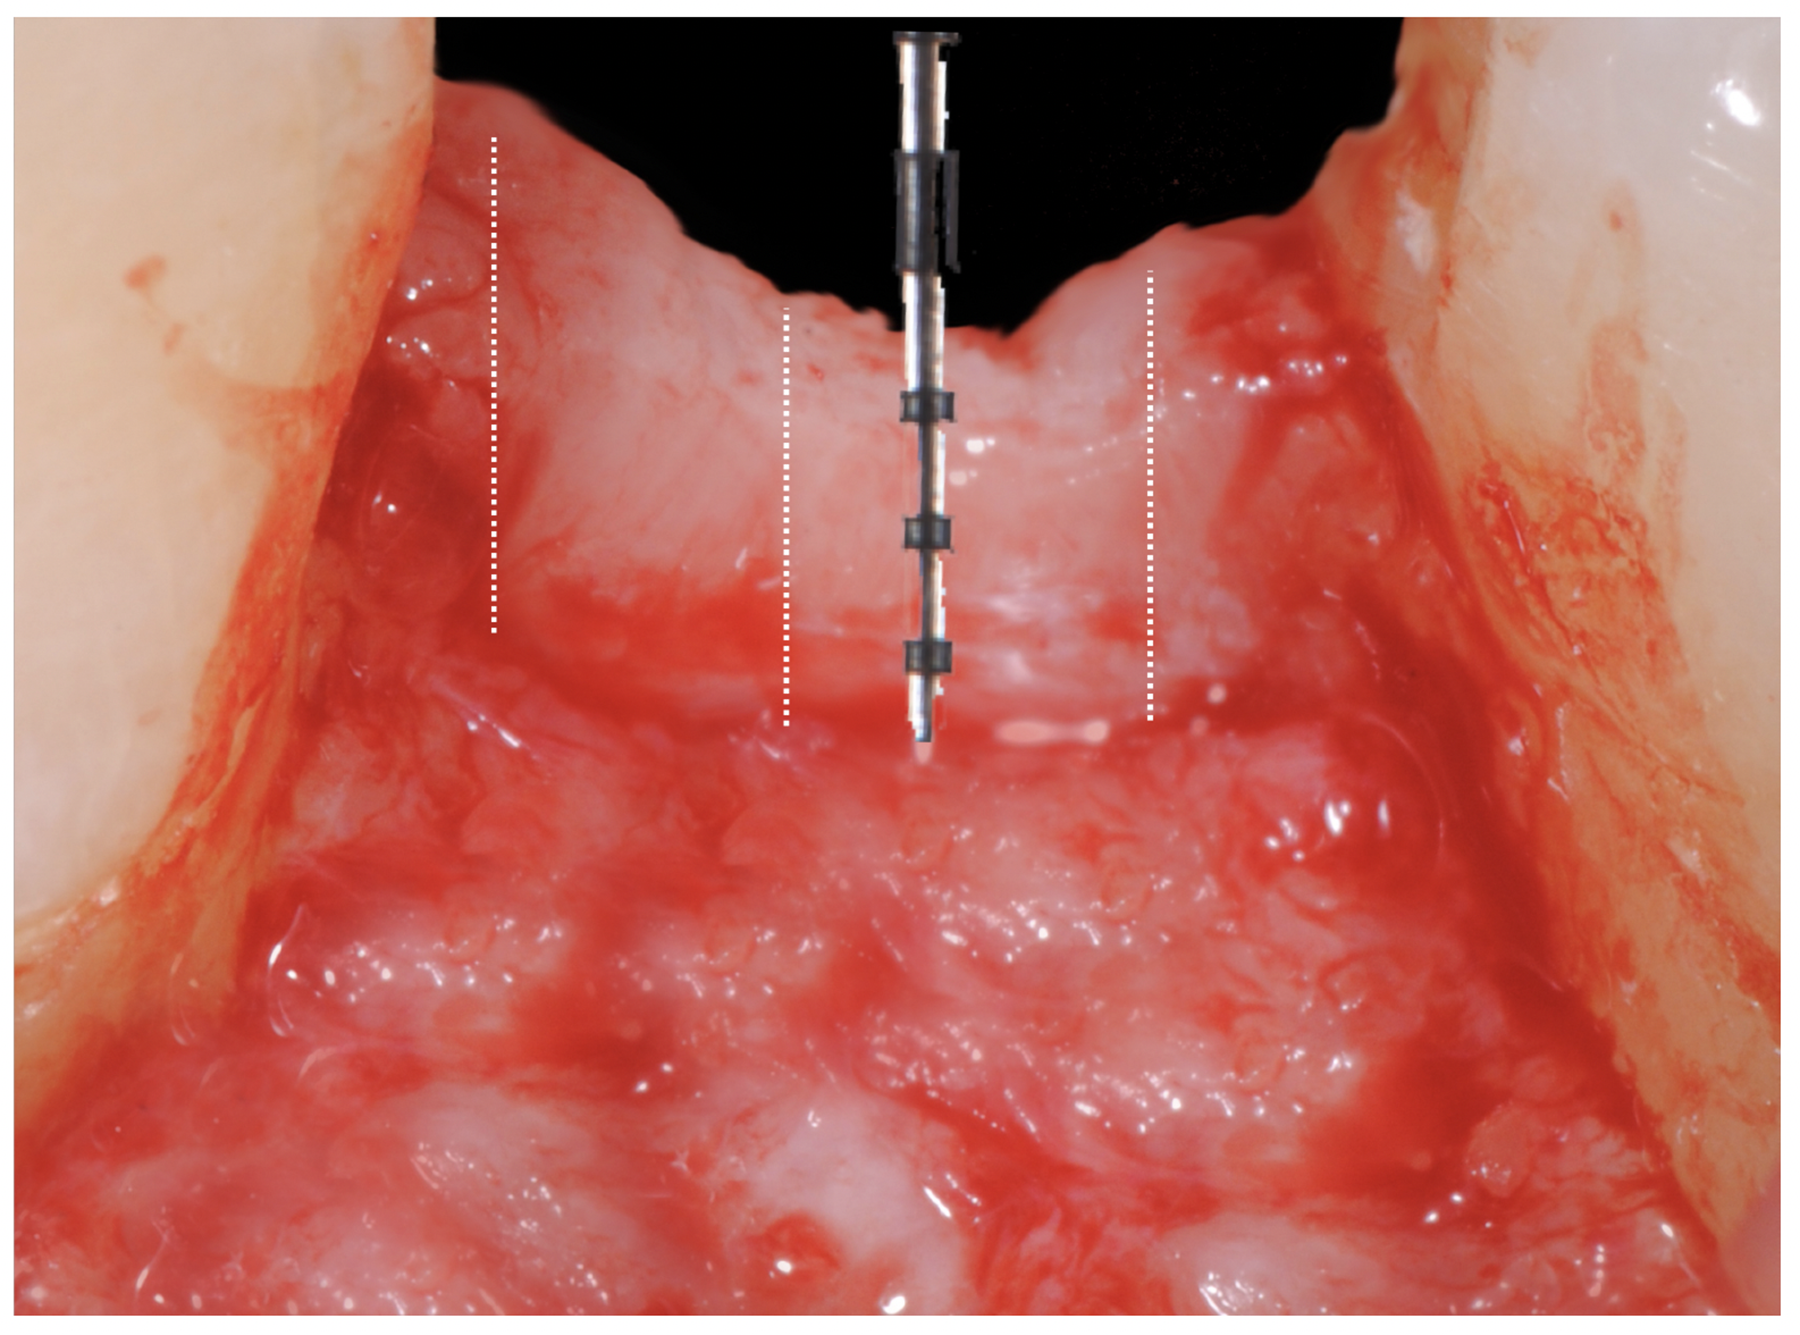

Tissue integration also depends on the surface properties of the materials in contact with peri-implant tissues, such as the surface energy and the decontamination and sterilization of the surfaces. Customized Computer-Aided Design/Computer-Aided Manufacturing (CAD/CAM) titanium and zirconia abutments may be fabricated using multiple technical procedures, all of which inevitably contaminate the surfaces of the materials, thus potentially compromising soft tissue integration and adherence.32 In vitro results have suggested that the decontamination of abutment surfaces is important for early fibroblast adherence and may improve the biological integration of peri-implant soft tissues.29 Ideally, abutments should have a surface that is completely decontaminated and sterilized, so as to allow for tight soft tissue adherence and integration in the subcritical and critical zones to support peri-implant tissues as well as create an effective soft-tissue seal/defense area against bacterial microorganisms. To achieve the best clinical performance in terms of soft tissue adherence, stock final abutments that are completely decontaminated and sterilized, with surface chemistry that boosts their biological response, should be the first choice (Figure 3 and Figure 4). These abutments are available in multiple heights, which should be selected based on the implant site, the vertical soft tissue thickness, and the esthetic expectations.

Finally, once the proper 3D position of the implants has been identified, the abutment placement protocol to be used should be evaluated. The "one abutment/one time" approach4,6,8,17 allows soft tissues to adhere firmly onto the surface of titanium abutments, thereby improving soft tissue response and bone stability (Figure 4 and Figure 7 through Figure 14 ). This approach avoids multiple connections and disconnections at the bone interface and favors undisturbed bone and soft tissue healing.4-7